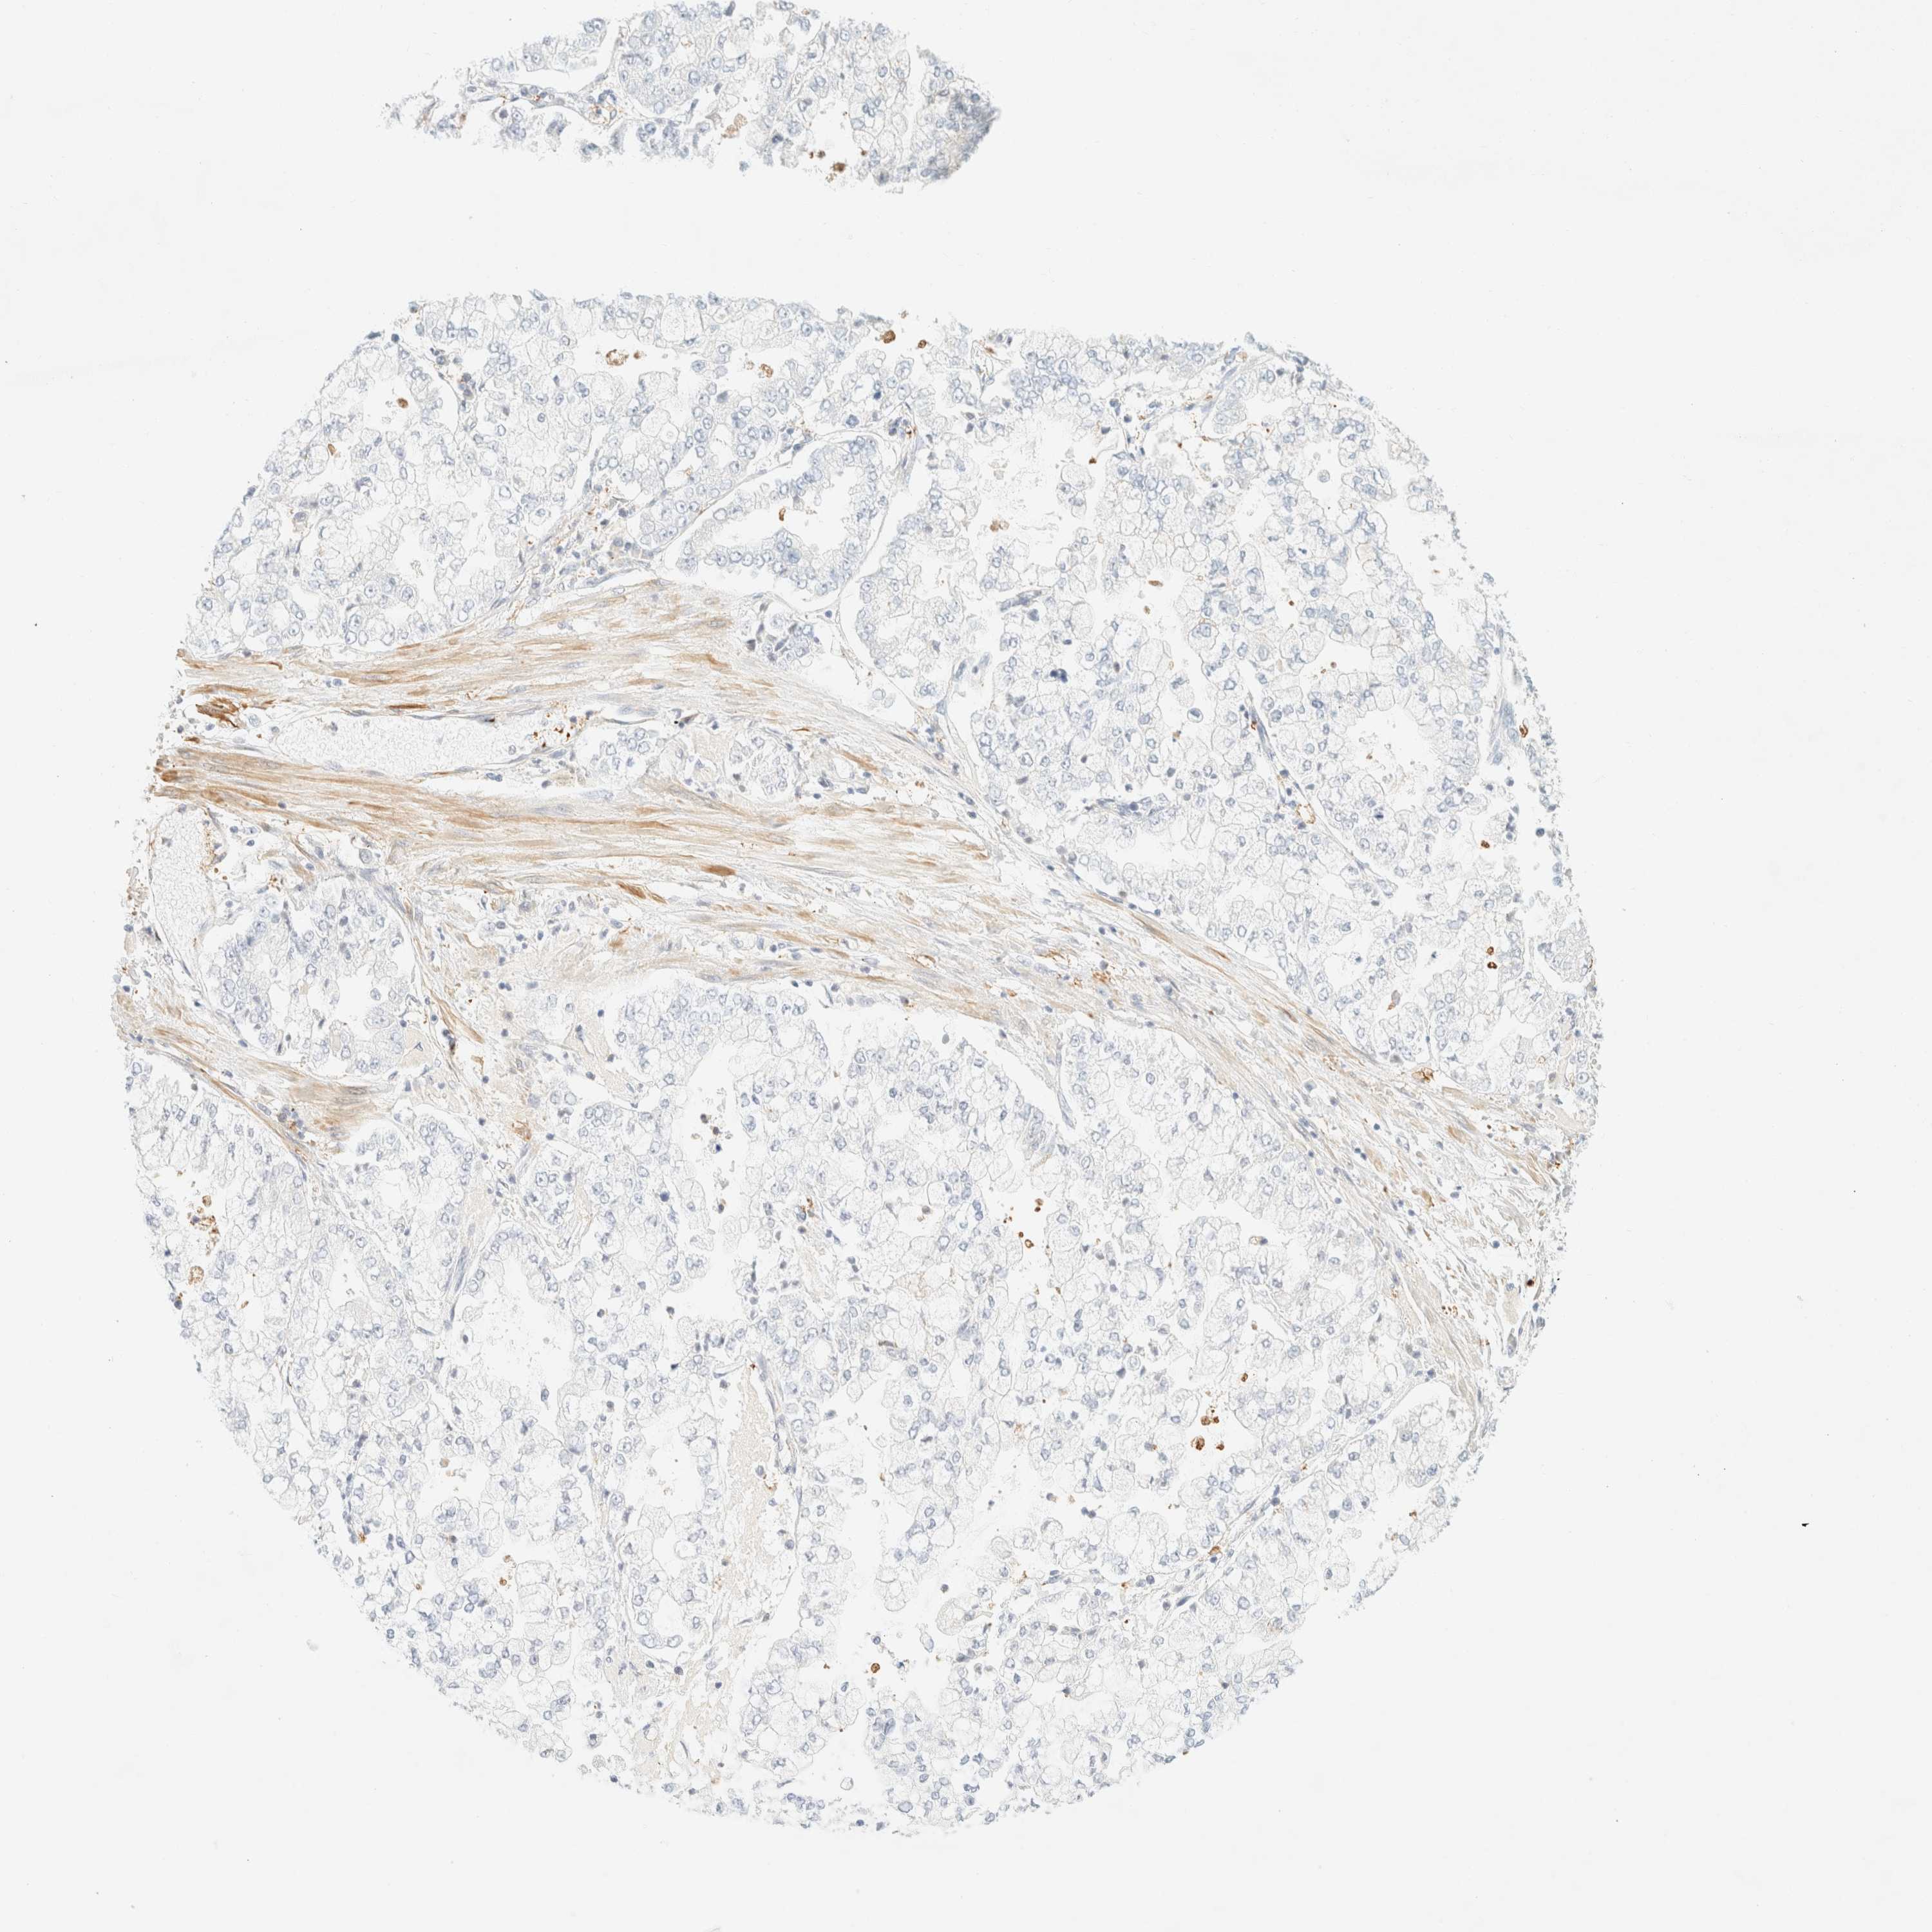

STOMACH CANCER - Protein expressioni

A mouse-over function shows sample information and annotation data. Click on an image to view it in a full screen mode. Samples can be filtered based on level of antibody staining by selecting one or several of the following categories: high, medium, low and not detected. The assay and annotation is described here.

Note that samples used for immunohistochemistry by the Human Protein Atlas do not correspond to samples in the TCGA dataset.

Antibody stainingi

Antibody staining in the annotated cell types in the current human tissue is reported as not detected, low, medium, or high, based on conventional immunohistochemistry profiling in selected tissues. This score is based on the combination of the staining intensity and fraction of stained cells.

Each image is clickable and will lead to virtual microscopy that enables deeper exploration of all samples and also displays staining intensity scores, fraction scores and subcellular localization as well as patient and tissue information for each sample.

Antibody HPA024524

Antibody HPA053090

Staining

High

Medium

Low

Not detected

Intensity

Strong

Moderate

Weak

Negative

Quantity

>75%

75%-25%

<25%

None

Location

Nuclear

Cytoplasmic/membranous

Cytoplasmic/membranous,nuclear

Adenocarcinoma, NOS